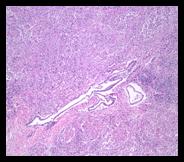

Summary: A 7-year-old, intact male, German Shorthaired Pointer

was submitted to ADDL following an acute history of respiratory distress,

prostatomegaly, tenesmus, and anorexia. At necropsy, the lungs were dark red

and non-collapsing with multifocal to coalescing, gray nodules widely

disseminated throughout all lung lobes. The prostate gland was expanded by

abundant pale tan soft tissue. Histologically, the lung and prostate were

expanded and infiltrated by granulomatous inflammation with intralesional

fungal yeasts, morphologically consistent with Blastomyces spp. |

Numerous thick-walled, buff-colored, spherical to ovoid, broad-based budding yeasts are scattered throughout granulomatous inflammation in the prostate gland and lung. The yeasts measure approximately 5-20 µm in diameter; findings are consistent with Blastomyces spp. |

| The normal prostate

architecture is replaced by aggregates of epithelioid macrophages and

multinucleated giant cells (granulomas). Few serous glands are

identifiable. The acinar epithelial cells are atrophied.